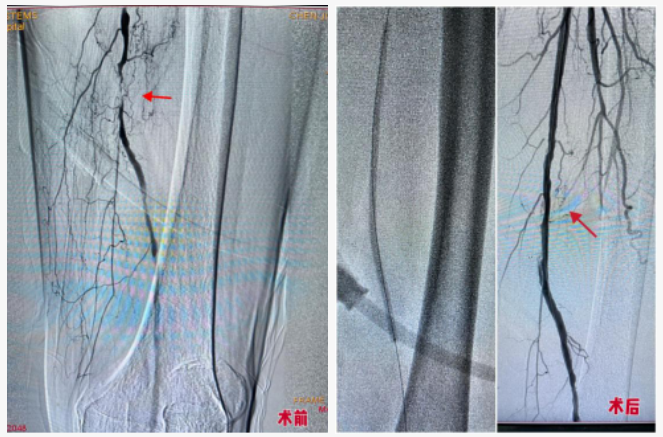

1. 左侧股浅动脉中段闭塞性病变

行左侧股浅动脉球囊扩张成形术,旨在开通闭塞血管,恢复下肢血流。

本例手术的核心难点在于患者病变血管存在严重钙化,范围从左侧股浅动脉中段延伸至腘动脉远端,这极大增加了腔内开通的难度和风险。朱席政主任团队凭借精湛技术和丰富经验成功完成了手术。